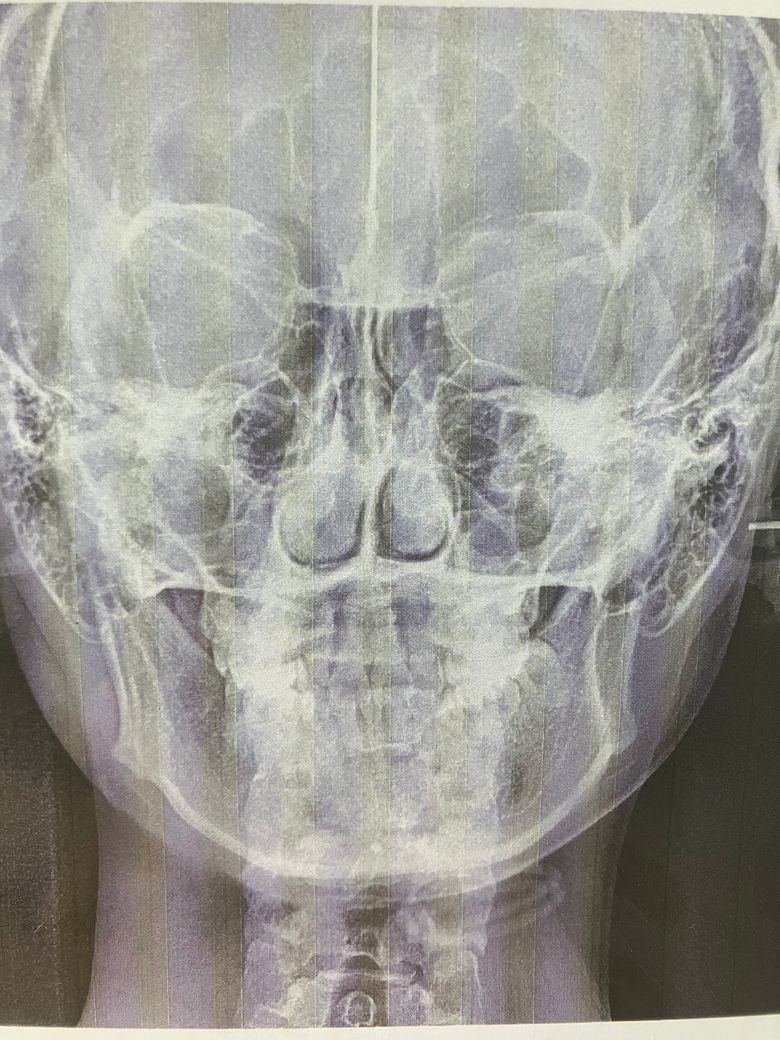

과개교합이 있다는데 어느정도라고 보시나요? 그 외에도 질문

현재 23살입니다. 과개교합이 있다고는 했는데 어느정도인지 궁금합니다.. 교정이 꼭 필요한지 궁금해요. 어금니 교합이 깊은 편인가요?

• 1번 째 사진

과개교합이 있는 것으로 보이며 그 외 치열상태를 봤을 때에도 적절한 교정치료가 필요해보입니다.

어금니 맞물림은 거의 정상에 가깝고, 위아래 앞니 과개교합이 다소 있습니다. 보통 1/4정도 위 아래 앞니가 아래 앞니를 덮는 것이 정상이나 지금보면 1/2이상 덮고 있습니다. 마모가 점차 심해지면 과개교합도 계속 심해집니다. 교정치료계획은 지금 이 자료만으로는 어떻게 진행된다 단정하기 어렵습니다.